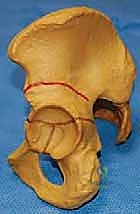

يقوم الجراح بإجراء قطع غير كامل في عظم الحوض (عظم الحرقفة) يمتد وصولاً إلى الغضروف ثلاثي الشعب (Triradiate Cartilage) الذي يكون مرناً لدى الأطفال. هذا الغضروف يعمل كـ "مفصلة" (Hinge). يتم بعد ذلك ثني سقف التجويف الحقي إلى الأسفل والخارج لتغطية رأس الفخذ من الجهة الأمامية الجانبية (Anterolateral).

تُعد هذه التقنية ممتازة للأطفال الذين يعانون من نقص شديد في التغطية الأمامية لرأس الفخذ، وعادة ما تُجرى للأطفال بين عمر سنة ونصف إلى 6 سنوات، قبل أن يتعظم الغضروف ثلاثي الشعب. للحفاظ على الوضعية الجديدة للسقف، يتم أخذ قطعة عظمية صغيرة (طعم عظمي - Bone Graft) من حوض الطفل نفسه ووضعها في مكان القطع كإسفين داعم.

في عملية ديجا، يتم قطع القشرة الخارجية لعظم الحرقفة مع ترك القشرة الداخلية سليمة لتعمل كمفصلة (Hinge). هذا يسمح للجراح بثني سقف الحُق إلى الأسفل بمرونة عالية، مما يوفر تغطية ممتازة لرأس الفخذ، خاصة من الجهة الخلفية الجانبية (Posterolateral).